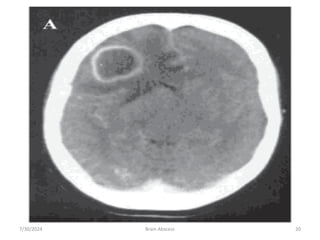

4. radiological characteristic of brain abscess

1. Brain CTS with contrast

• ring enhancement

• Multi loculation

• Multiplicity

• Finding of gas

7/30/2024 Brain Abscess 17